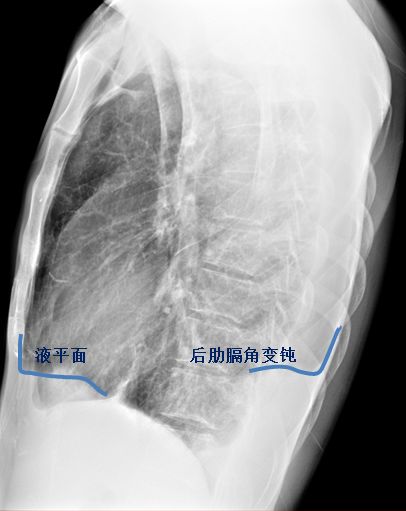

病例2患者的X线胸片

黑色区域:无肺纹理区域。肺叶压缩约70%;

蓝色虚线:被压缩肺组织边缘;

紫色箭头:肋膈角可见液-气平面;

橙色实线:第3、4肋骨前端骨桥关节,肋骨骨桥(先天变异);

可见心影及纵隔向对侧轻度移位。